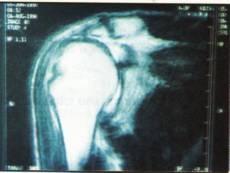

RESONANCIA MAGNETICA

Resonancia magnética

Corte sagital

Resonancia magnética Corte axial

Corte coronal